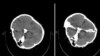

این گزارش در حالی منتشر می شود که خبرگزاری فارس -نزدیک به سپاه پاسداران- در روز ۲۸ شهریور، اصالت تصاویر سی‌تی‌اسکن مغزی مهسا امینی را که یک گروه هکری یافته و منتشر شده بود، تأیید کرده اما مدعی شده بود که «هیچ شواهدی از ضربه به سر و خون‌ریزی در این تصاویر به چشم نمی‌خورد».

در آن زمان شماری از متخصصان از جمله رئیس شورای هماهنگی نظام پزشکی استان هرمزگان پس از بررسی این تصاویر، جان‌باختن مهسا امینی را از عوارض ناشی از ضربه مستقیم به جمجمه عنوان کرده بودند.